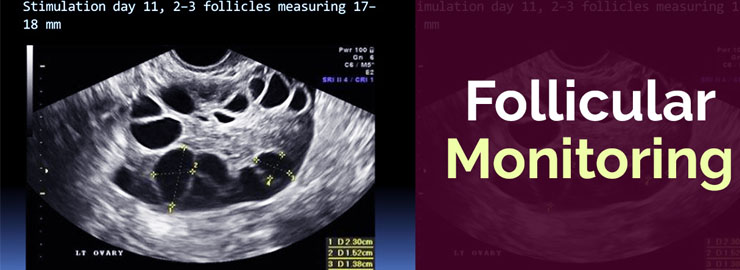

Follicular Monitoring

It is a simple technique used by gynecologists for assessing ovarian follicles at regular intervals for tracking and documenting ovulation in women who are trying to get pregnant.

It is a serial ultrasound done mostly by transvaginal route.

Follicles are not oocytes. The follicle is a functional anatomical structure which forms part of the ovary and the egg is the cell that will mature in a microscopic part of the inner wall of a follicle over spontaneous or stimulated ovarian cycle in normal conditions .It also contains other cell types which produce estrogen required for normal development of egg maturation